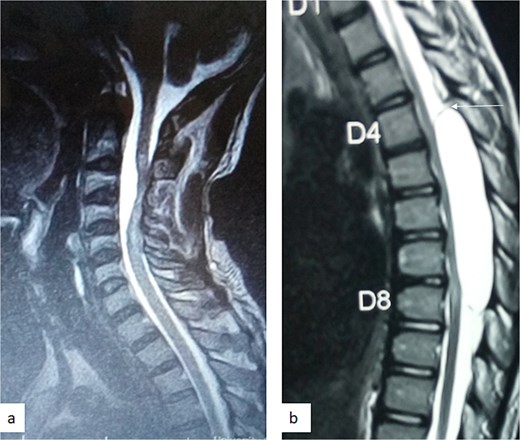

A 12-year-old girl presented to us with progressive weakness of the lower limbs of 11 months duration. There was associated paraesthesia and spasms but no sphincteric dysfunction. Clinical examination revealed an otherwise healthy young girl with normal mental status. She had spastic paraparesis (power Grades 3 to 4) and exaggerated muscle stretch reflexes in the lower limbs. The sensory level was T4. There was no gibbus or spinal tenderness. Other systemic examination findings were normal. A clinical diagnosis of T4 non-traumatic myelopathy, Frankel D was made. Thoracic spine MRI showed an extradural lesion with similar intensities to CSF on all sequences posterior to the spinal cord at T4–T8 as well as significant cord compression at the same levels (Fig. 3) [12]. A diagnosis of thoracic spine EAC was made. We approached the lesion through T4–T8 laminectomies. Intra-operative finding was that of a large extradural cyst which communicated with the subarachnoid space through a dorsolaterally located pedicle near the nerve sleeve at T7. The cyst was excised completely and the dura defect closed without duroplasty (Fig. 4) [12]. The post-operative course was uneventful and she was discharged on the 24th post-operative day. She was last seen 48 months post-surgery. At the time, she was ambulating without support with power of Grade 5 in the lower limbs.

Sagittal T1-weighted (a) and T2-weighted (b) thoracic spine MRI showing an extradural cyst at T4–T8 compressing the cord anteriorly [12].

MRI is the imaging modality of choice for the diagnosis and follow-up of SACs [4]. It does not require intrathecal injection of contrast and demonstrates the location, size, extent, and nature of the cysts as well as neural elements compression and intrinsic cord changes among other features [7, 16–18]. On MRI SACs have similar signal intensities to those of CSF, hypointense on T1-weighted, and hyperintense on T2-weighted images [16]. Extradural cysts may show absent posterior epidural fat, epidural fat capping, and T2-hypointense cyst wall [16, 19, 20] (Figs 3 and 6b). Intradural cysts are characterized by widening of the subarachnoid space, displacement of the cord/cord compression and an undistinguishable cyst wall [2, 21] (Fig. 1). The site of communication between the cysts and subarachnoid may not be demonstrable on MRI [16]. Computed tomography myelograghy has been the imaging of choice in demonstrating the communicating site between the cyst and the subarachnoid cyst [16]. Newer MRI flow studies using cinematic MRI has proven to also be able to demonstrate the communication site [22].